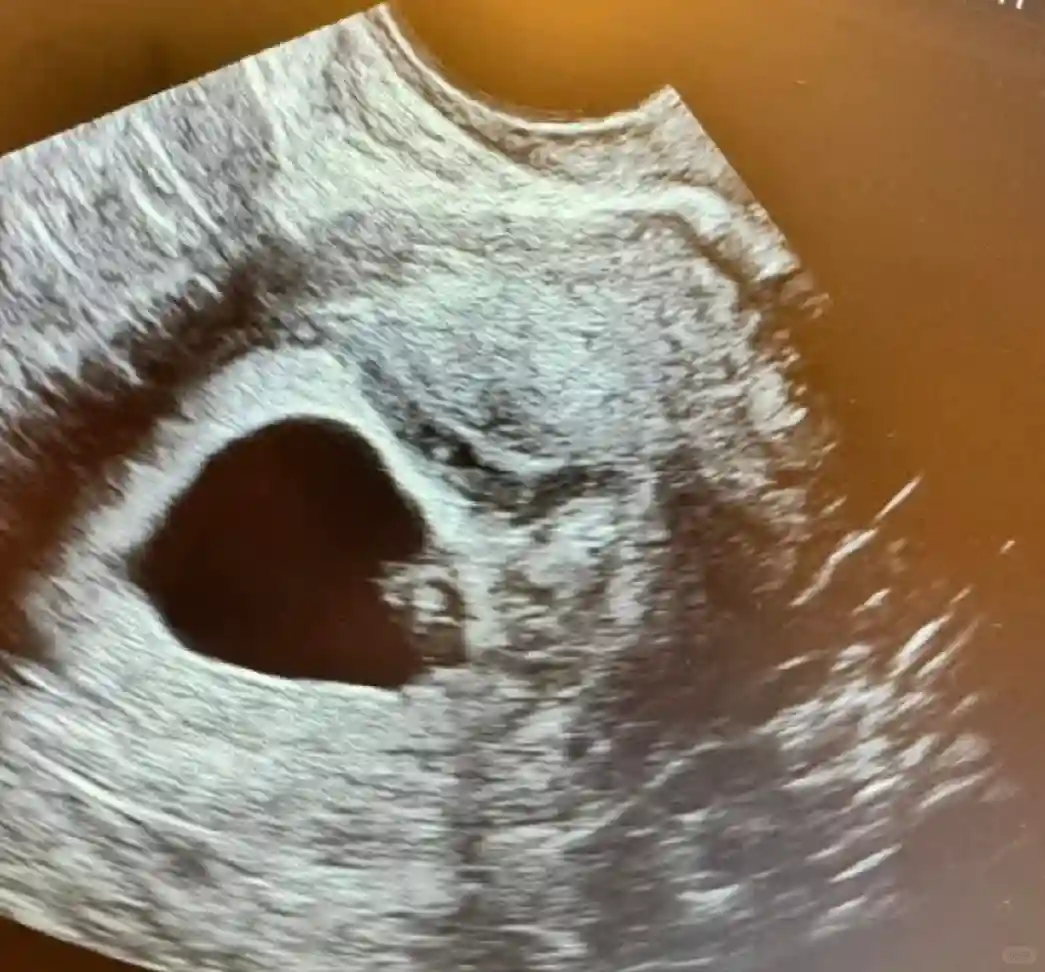

放了一颗4bb,记得当天约的是早上9点半,从8点我就开始猛猛喝水 ,因为要做b超,需要膀胱充盈,超级憋,搞的我特别紧张,现在记录下来都会回想到当时的心情。 整个过程很快,都不要打麻,10分钟左右就搞定了,b超上可以看到一个亮亮的小点注入到子宫。然后就完成了,不要剧烈运动,也不要熬夜,一定要保持心情愉悦! 过12天后就可以去测HCG